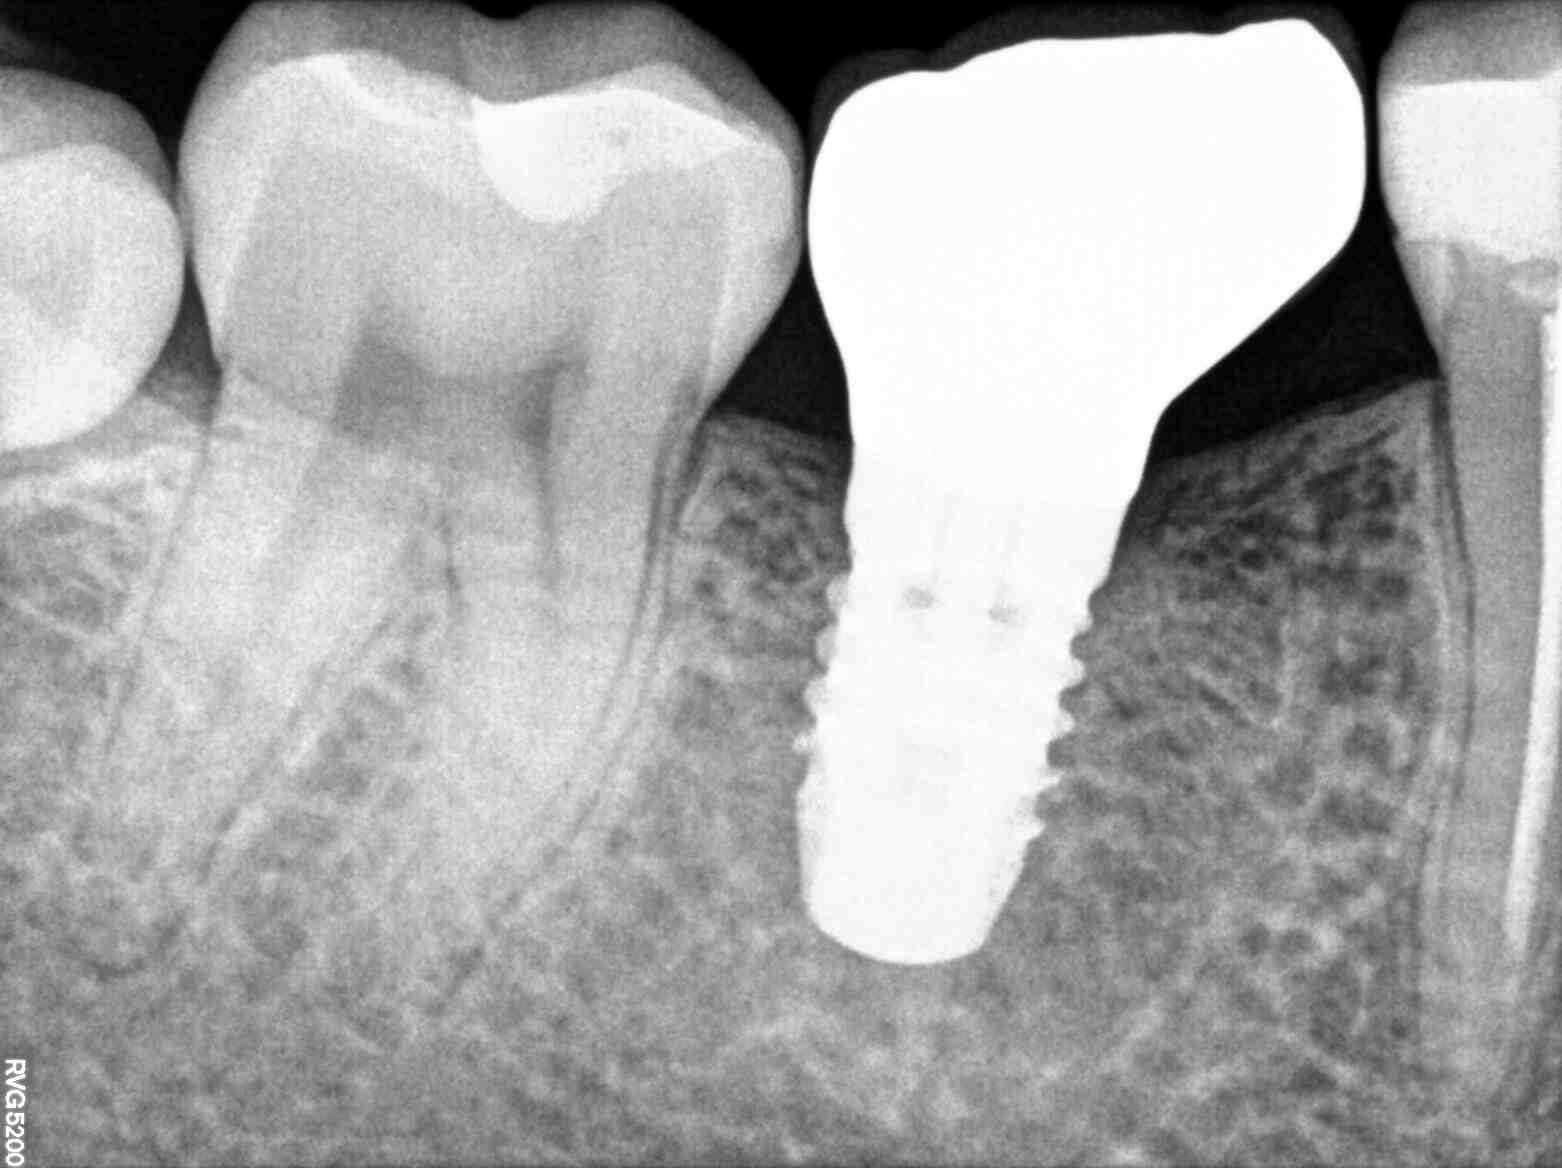

Twój start w implantologii: Jak unikać błędów i przewidywalnie pozycjonować implanty?